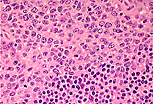

皮质区的淋巴样滤泡

是B细胞免疫应答的发生部位。

在常规形态学观察中可识别出: 中心母细胞 、 中心细胞 、 滤泡树突状细胞 、 巨噬细胞 、 小淋巴细胞 。 |

滤泡树突状细胞可通过其大而淡染的卵圆形细胞核识别,核内可见一个小核仁,这类细胞常两两聚集分布。 |

中心母细胞可通过其大而圆形的淡染细胞核识别,核染色质稀疏,可见数个偏位的核仁(常靠近核膜)。

中心细胞的细胞核更小,呈有裂沟状,染色质更致密。 |